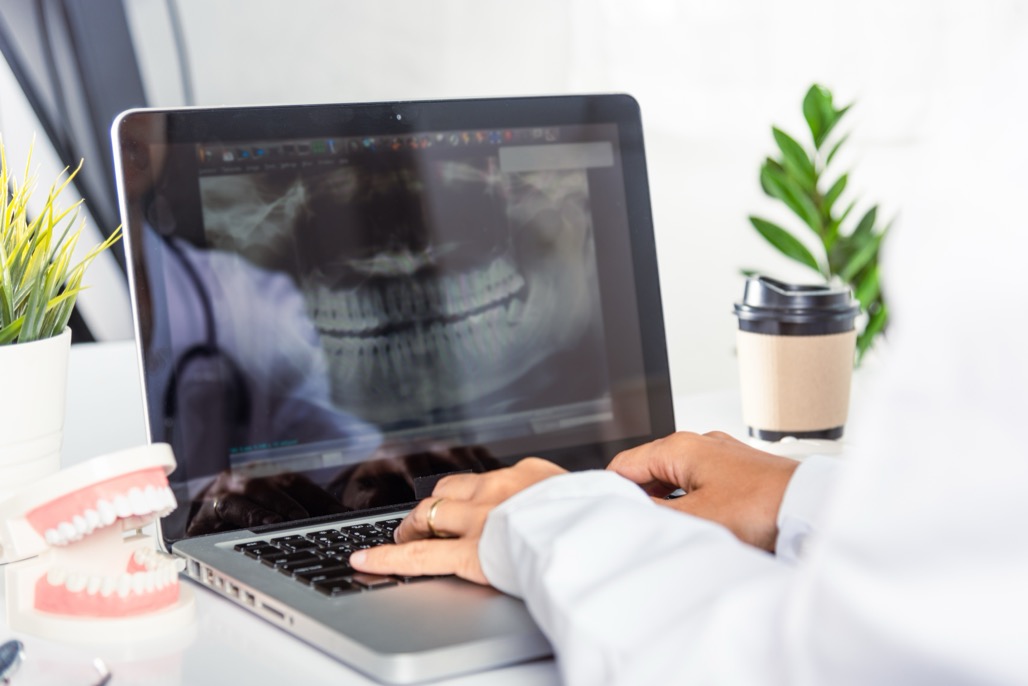

Dental Implant Specialist Dental implants are artificial teeth that replace your missing teeth. The implant procedure involves a surgery that is moderately invasive, and not all dentists are able to perform it. If you are looking for a dental implant specialist, this page helps you find the right one. What kind of dentist performs a …

Dental Implants Simply put, a dental implant is an artificial tooth root. A dental implant takes the place of an extracted tooth root. The root is surgically placed to hold an artificial tooth such as a crown or bridge. Most dental implants are made of titanium, a few are ceramic. Titanium and ceramic are safe …